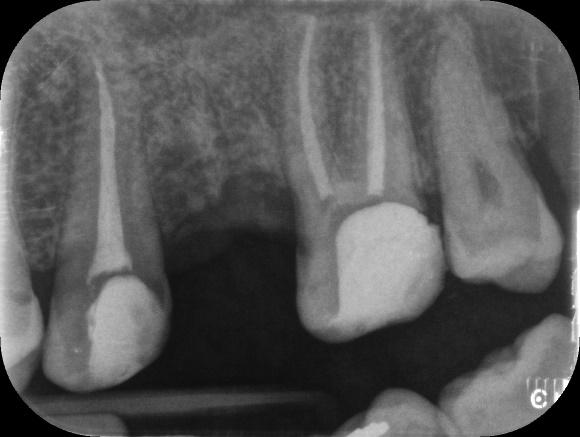

Upper Premolar curved root Primary root canal treatment